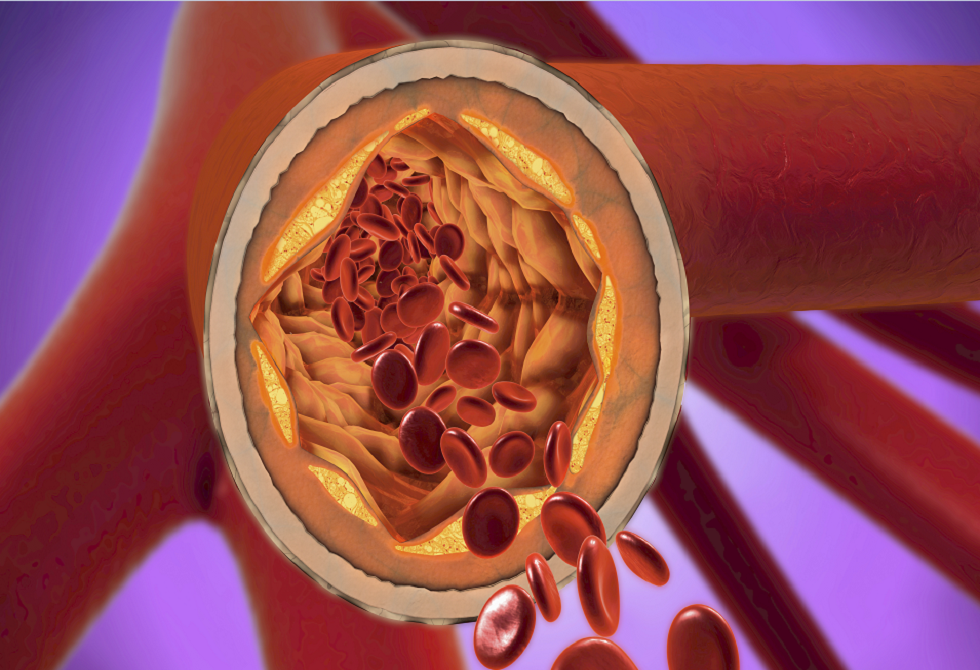

دراسة تحذر: السمنة وراء تفشي معظم الأمراض المزمنة

أثبتت دراسة حديثة أن السمنة تلعب دورا رئيسيا في الإصابة بمعظم الأمراض المزمنة الشائعة والخطيرة.

وحلل فريق من جامعة إكستر 71 حالة مرضية غالبا ما تتزامن لدى الأفراد، مثل داء السكري والتهاب المفاصل، بهدف تحديد ما إذا كانت السمنة عامل خطر أساسي.

واستخدم الباحثون بيانات جينية وصحية لآلاف المشاركين في دراسات سابقة. ووجدوا أن السمنة – المعرّفة بمؤشر كتلة الجسم (BMI) الذي يزيد عن 30 – تساهم في 61 حالة من أصل 71، أي ما يقارب 86%.

وأظهرت النتائج أنه من بين كل 1000 شخص مصاب بمرض الكلى المزمن وهشاشة العظام، يمكن أن يمنع خفض مؤشر كتلة الجسم بمقدار 4.5 نقطة حوالي 17 شخصا من الإصابة بالمرضين معا. كما أن الخفض نفسه قد يمنع حوالي 9 أشخاص من بين كل 1000 شخص من الإصابة بداء السكري وهشاشة العظام.

وأوضح الباحثون أن السمنة تفسر جميع حالات التداخل الجيني في عشرة أزواج من الأمراض، ما يدل على أنها العامل الرئيسي وراء حدوثها معا. وتشمل هذه الأزواج: مرض الكلى المزمن مع أمراض الرئة المزمنة، والنقرس مع انقطاع النفس النومي، ومرض الكلى مع هشاشة العظام، وداء السكري مع هشاشة العظام.

وقال البروفيسور جاك بودن، قائد الدراسة وعالم بيانات الطب الحيوي: "لطالما عرفنا أن بعض الأمراض غالبا ما تحدث معا، وأن السمنة تزيد من خطر الإصابة بالعديد منها. وتعد هذه الدراسة الأولى من نوعها التي تستخدم علم الوراثة لتحديد دور السمنة في الإصابة بالأمراض لدى نفس الأفراد".

وأضاف: "لقد وجدنا أن السمنة هي العامل الرئيسي المسبب لبعض الأمراض، ويتيح بحثنا للأطباء تقديم نصائح أكثر تحديدا للمرضى لمساعدتهم على الوقاية".

وأكدت البروفيسورة جين ماسولي، استشارية طب الشيخوخة، أن الدراسة تعزز الحاجة لمعالجة السمنة عبر برامج الصحة العامة، مشيرة إلى أن إدارة الوزن مدى الحياة تعد جزءا أساسيا من استراتيجية هيئة الخدمات الصحية الوطنية البريطانية للوقاية من تراكم الأمراض المزمنة، وهو ما يساعد الناس على عيش حياة أطول وأكثر صحة.